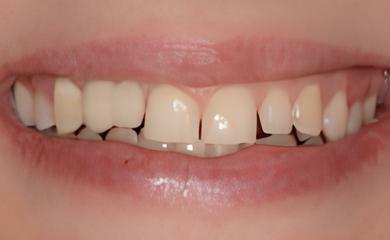

IMPLANTOLOGIE: LES IMPLANTS DANS LE SECTEUR ESTHÉTIQUE